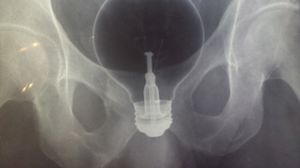

Un barbat s-a prezentat cu un bec in anus, iar potrivit spuselor medicilor, becul s-a spart in momentul in care a fost extras.